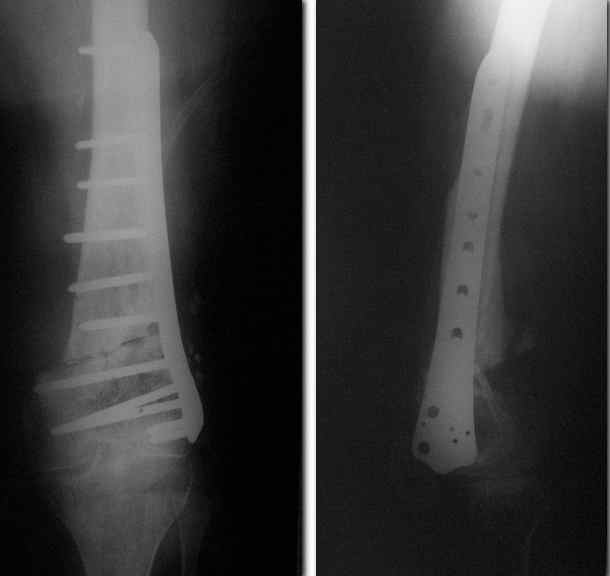

Пример подобного ложного сустава в приложении.

На сегодня есть имплантаты с куда более продвинутой дистальной фиксацией.

Да практически у всех производителей есть сегодня бедренные стержни с возмоностью ввести винты максимально дистально, и более 2. Это и Synthes, и Stryker, и DePuy, и ChM, и даже предприятие "ЦИТО". Единственное - диаметр винтов. Желательно больше 5 мм.

Выглядит красиво. А движения в колене какие были на столе?

Была контрактура и спаянный с суставной поверхностью надколенник. Сделали до синтеза редрессацию. Достигли почти полного объема движений.